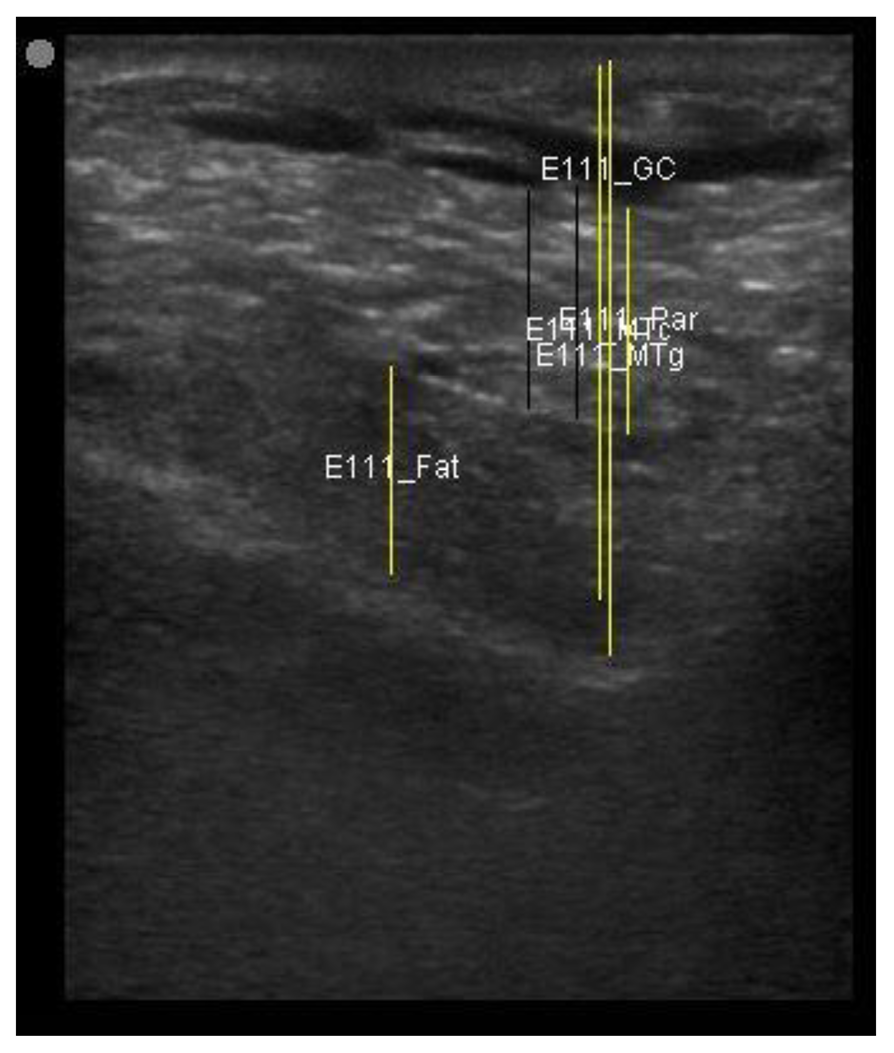

| 113 days of pregnancy (P113) Scanning depth 4.7 cm | ![]() | ![]() | MT generous: 28.9 mm MT conservative: 25.9 mm Gland cistern: 3.3 mm Parenchyma: 10.9 mm Fat Pad: 10.0 mm |